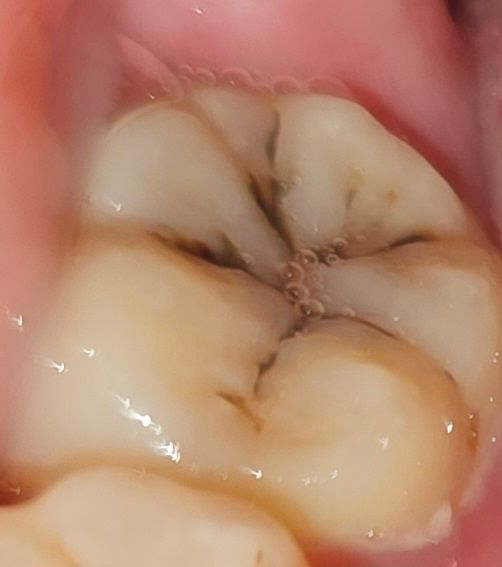

치과는 여력이 없어서 그동안 못 갔었고... 왠지 턱이 뻐근하고 거슬려서 봤더니 누가 봐도 치료가 필요할 만큼 충치가 확실히 보이는 정도였는데 (심한 거 압니다)

씹을 때 욱신거리지는 않는 충치인데 턱에 통증을 줄 수도 있나요? 씹을 땐 정말 안 아픈데 신경치료일 가능성 있나요

• 1번 째 사진

저 정도 충치는 신경치료 하지 않고 떼우는 것이 가능할 것으로 보입니다. 정확한 것은 치과에 가서 x-ray 찍어야 알 수 있습니다.

사진으로 보이는 충치만으로는 통증이 심하지 않을 것으로 생각됩니다. 결과적으로 턱관절에 가해지는 힘이 강해서 생기는 턱관절 질환일 가능성이 높습니다. 자세한 확인을 위해서 치과에서 진료를 받아보세요